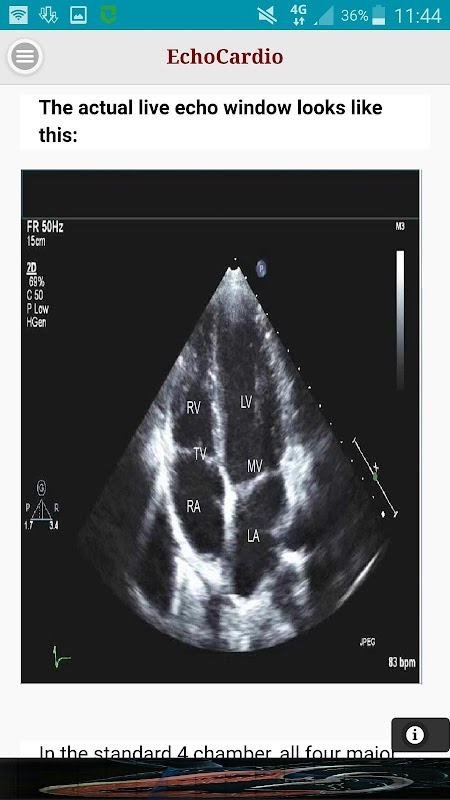

Apical